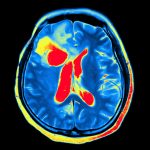

My sister, Dad, and I waited in the doctor’s office before Christmas for his deep brain stimulation (DBS) appointment. Dad underwent DBS last fall, and it’s time for a “tuneup,” as he likes to call them. I imagine his doctor with a wrench in her hand, manipulating Dad’s brain like a mechanic fixes a car.

If she works on the suspension on the left side, maybe it’ll change the tremors in his left foot. And it does. His doctor punches the instructions into her computer and my dad’s foot stops shaking. It’s an immediate change. We don’t have to wait for medications to kick in or his body to adjust.